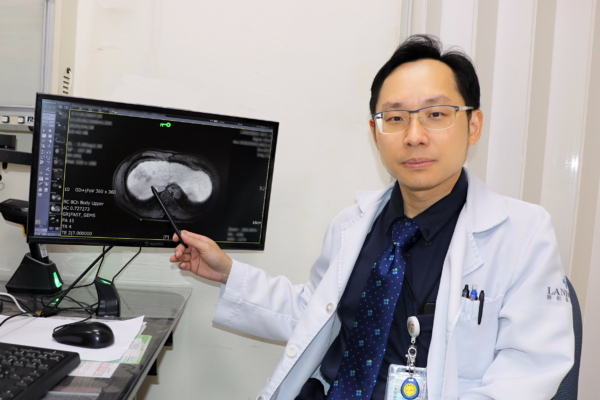

隨著2023年免疫標靶治療納入健保給付,大幅降低患者經濟負擔,也讓更多中晚期癌友得以接受有效治療。聯新國際醫院腸胃肝膽科余青殷醫師分享一位六十五歲患者,於兩年前接受肝癌切除手術,在術後例行追蹤時,發現甲型胎兒蛋白指數(AFP)持續飆高,以及肺部出現轉移的現象,經評估自體免疫狀況後,醫療團隊決定使用免疫標靶治療,採用第一線免疫標靶聯合療法-免疫藥物「癌自禦」與標靶藥物「癌思停」合併治療,三個月後AFP指數恢復正常,癌細胞亦完全消失,患者未出現任何不適或併發症,生活品質如常。

余青殷指出,過去中晚期肝癌的治療主要依賴單一標靶口服藥物,療效有限;而隨著免疫標靶聯合治療的發展,病患的整體存活期已顯著延長至近20個月,死亡風險亦降低約三成。值得注意的是,約10%以下的患者有機會成功治癒,讓腫瘤完全消失,這是以往中晚期肝癌不容易達到的效果。